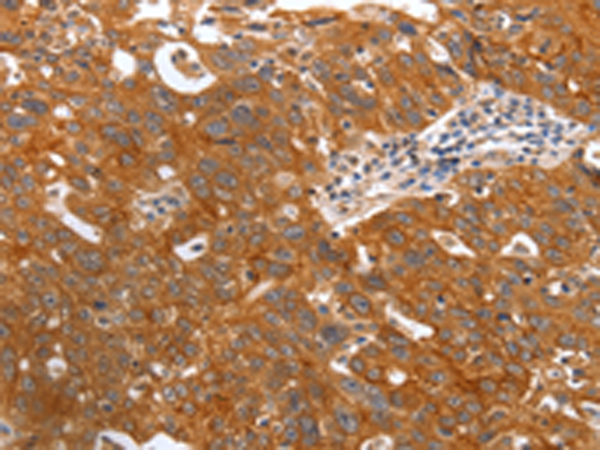

分类: 科研抗体货号: P07530别名: TFAR19应用: IHC反应种属: Human, Mouse